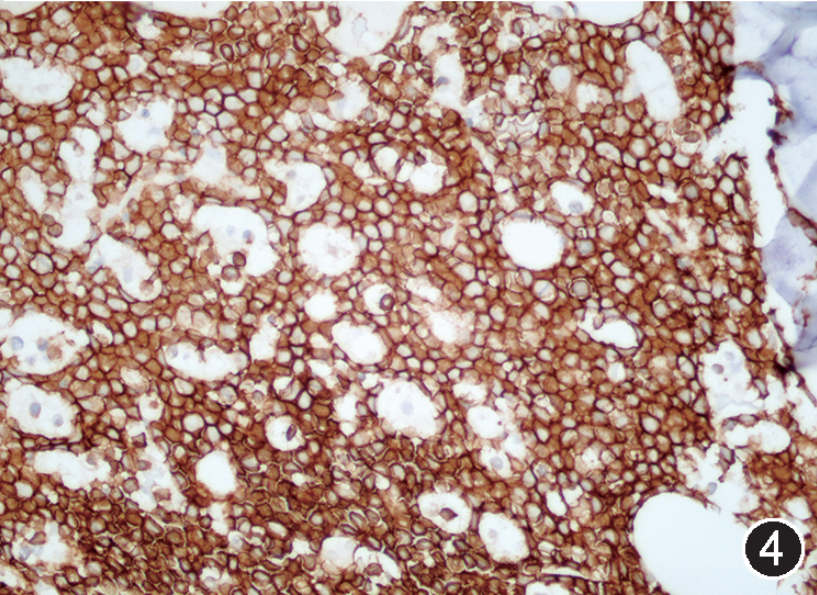

图注:图1 骨髓涂片中的肿瘤细胞(瑞氏染色,×1 000);图2 骨髓活检中的肿瘤细胞(HE, 高倍放大);图3 免疫组织化学染色,CD20部分阳性(EnVision法,中倍放大);图4 免疫组织化学染色,CD19阳性;图5 免疫组织化学染色,CD10阳性;图 6 免疫组织化学染色,MYC阳性,图 7 免疫组织化学染色,bcl-2阴性;图 8 免疫组织化学染色,Ki-67阳性指数约 80%。

根据以上检查结果,需要考虑的淋巴瘤类型包括BL、HGBL、原始细胞标记阴性B-ALL(占B-ALL<5%)以及罕见CD5-CD10+MCL的母细胞变型,须进一步进行免疫组化(包括CyclinD1、CD10、BCL6、MUM1、MYC、BCL2、Ki67)、染色体核型、FISH检测(MYC、BCL2、BCL6、IgH-CCND1)以及白血病融合基因检测加以区分。最终流式细胞学示肿瘤细胞CD38强表达、表达sIgM、sIgD和胞膜Kappa,免疫组化CyclinD1-,细胞遗传学示复杂核型,FISH检测MYC和bcl-6基因重排阳性,白血病52种融合基因阴性,二代测序提示存在TP53、CCND3、MYC、TCF3、FOXO1等HGBL、DLBCL中而非B-ALL/LBL中的常见基因突变类型,因此综合诊断为HGBL伴MYC和bcl-6基因重排。